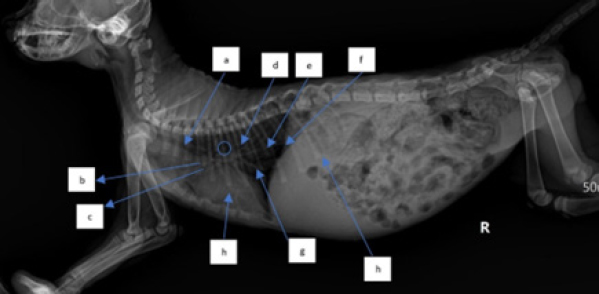

In examining the size of the heart via dorsoventral X-ray, the method used is a comparison of the width of the heart and the width between the right and left ribs and the comparison of the length of the boundaries of the right and left ribs with the heart. The measurement results in (Fig. 6) show a comparison of the length of the border of the right and left ribs with the heart RL, the length of the border between the ribs and the heart on the dexter and sinister parts is not the same (abnormal). In measuring the comparison of the width of the heart and the width between the right and left ribs, length B is greater than 2/3 A (abnormal), whereas normal is BA (Holland, 2020).

When evaluating the cardiac dimensions through dorsoventral X-ray analysis (Birsan et al., 2017), a technique employed involves assessing the heart’s width relative to the space between the right and left ribs, as well as comparing the length of the right and left rib margins concerning the heart. The findings in Figure 6 indicate a comparison between the length of the border of the right and left ribs against the heart RL. Notably, there exists an abnormality in the length of the border between the ribs and the heart on the dexter and sinister parts, as they are not of equal dimensions. According to Holland (2020) findings, aberrant results were obtained when assessing the ratio of the width of the heart to the width between the right and left ribs, with length B being greater than 2/3 A. In contrast, a normal outcome was observed when the ratio of B to A was within typical parameters.

Fig. 3. Thoracic radiograph of Hiro’s cat in a lateral position with a dilated heart with an enlarged heart size. (a). Trachea, (b). cranial pulmonary artery, (c). pulmonary vein, (d). aorta, (e). pulmonary caudalis arteries and veins, (f). diaphragm, (g). vena cava caudalis, and (h). ascitic fluid.

The way to measure the heart with the vertebrae heart size (VHS) method is by measuring it by drawing straight lines on the short axis and long axis (James, 2000), then the measurement results are aligned with the vertebrae and starting from the 4th rib (Marbella et al., 2023) then add up by looking at how long the vertebrae are. The normal size of VHS in the Buchanan and Bucheler method is 7.5 vertebrae (VT). In the case of Hiro’s cat (Fig. 6). VHS size using the Buchanan and Bucheler method (Litster and Buchanan, 2000) is 8 vertebrae with a long axis of 4.5 VT and a short axis of 3.5 VT so that the total becomes 8 VT (larger than normal size).

Fig. 6. Method of measuring the heart in the DV position (Left). Heart measurement with the VHS method of the Buchanan and Bucheler methods (Right).

During the X-ray examination, heart measurements were taken to identify any changes in the size of the heart organ. The lateral view measurements resulted in an intercostal measurement technique score of 4, with a normal range of 2.3–3.5. The height from the apex to the vertebral column was also measured compared to the carina, resulting in A being greater than 1/3 A + B and B being greater than 2/3 A + B (normal values are A < 1/3 A + B and B < 2/3 A + B). The VHS was also measured, and there was an increase in VHS results in CHF cases as mentioned in previous research in cats (Smith et al., 2004; antecedent corticosteroid administration has been noted in cats with congestive heart failure (CHFLaudhittirut et al., 2020), resulting in a score of 8 VT (the normal value is 7.5 VT). Measurements were then taken using the dorsoventral position, resulting in the heart size being different in R and L distances, with L being larger than R. The size of B was also greater than 2/3 (normally, R is equal to L, and B is less than 2/3). From these measurements, it was determined that the heart was enlarged or experiencing cardiomegaly. Cardiomegaly is the heart’s compensation for heart failure to meet the body’s circulatory needs, which can be caused by congestive heart failure (CHF), valvular heart disease, and cardiomyopathy (Triakoso, 2020).